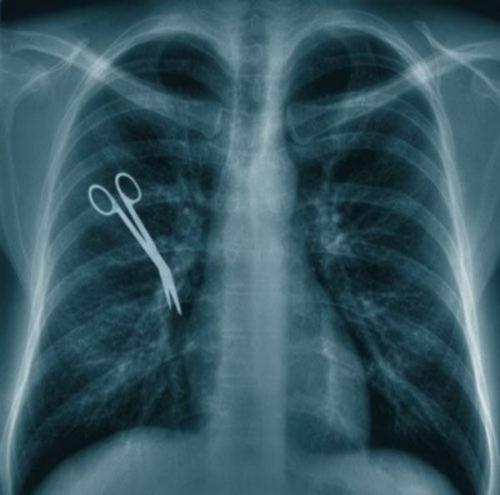

Предметы, которые можно обнаружить в человеке благодаря рентгену

Внутри человека с помощью рентгенологического оборудования можно обнаружить массу оригинальных предметов, причем порой даже несовместимых с жизнью.

Хирургический инструмент